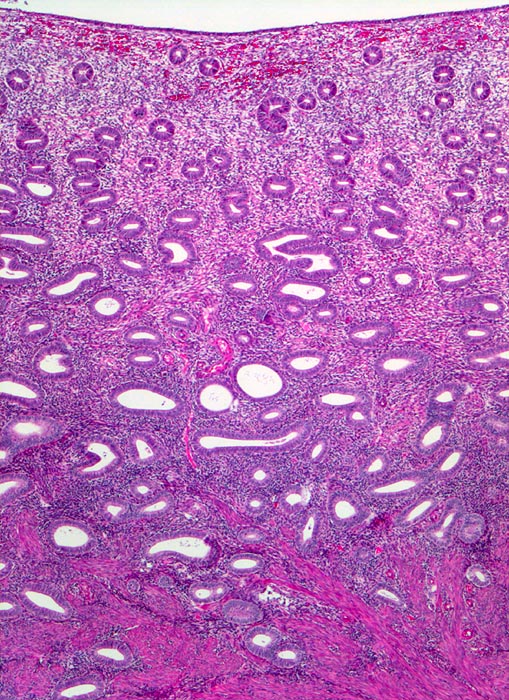

Myome imponieren makroskopisch typischerweise als runde, scharf begrenzte und nicht bekapselte Knoten. Die Schnittfläche ist weiss mit wirbliger Struktur. Mikroskopisch ist der Tumor aufgebaut aus Bündeln (=Faszikeln) spindelförmiger Zellen mit reichlich dunkel-eosinophilem Zytoplasma und an den Enden abgerundeten länglichen, zigarrenförmigen Kernen. Zell- und Fasergehalt sind sehr variabel. Degenerative Veränderungen wie Verkalkungen (> 4280), hyaline Nekrosen, Einblutungen, Homogenisierung des Kollagens, Ödem oder myxoide Degeneration und Zystenbildung (> 4279) kommen häufig vor. Manche gutartigen Leiomyome können ein einzelnes Malignitätskriterium aufweisen (vermehrte Mitosen, hohe Zellularität, deutliche Zellatypien oder Nekrosen). Falls mehr als eines dieser Kriterien vorhanden ist, handelt es sich differentialdiagnostisch um einen leiomyomatösen Tumor mit unsicherem Malignitätspotential (STUMP=Smooth Muscle Tumor of Uncertain Malignant Potential) oder um ein Leiomyosarkom. In seltenen Fällen lässt sich die Dignität nicht sicher bestimmen.

• Zwei scharf begrenzte Knoten im Myometrium bestehend aus Bündeln glatter Muskulatur.

• Variabler Anteil Fibrose (Kollagenfasern).

• Glatte Muskelzelle: eosinophiles Zytoplasma, längliche Kerne mit abgerundeten Enden (zigarrenförmig).

• Das Endometrium über dem Leiomyom ist druckatroph, das übrige Endometrium zeigt Proliferationszeichen.